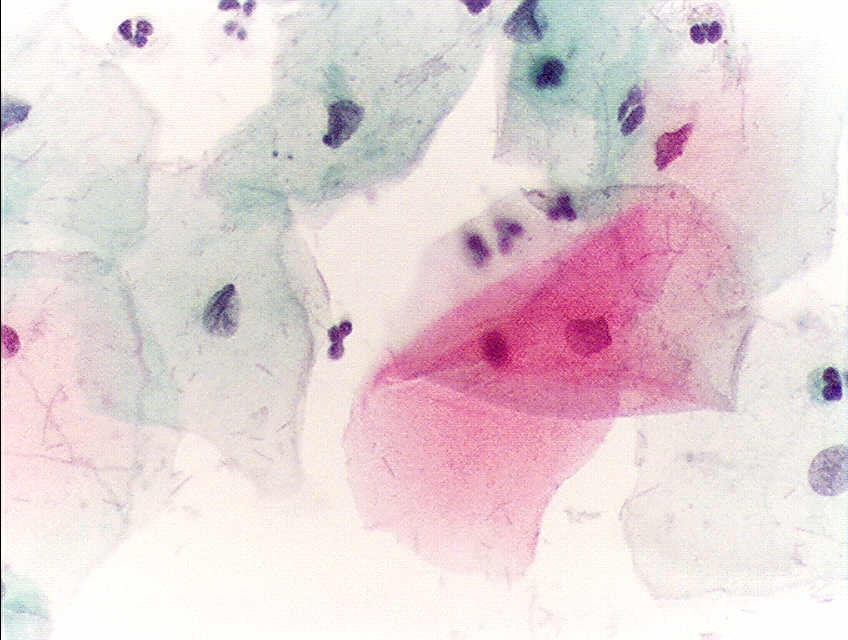

Σήμερα το τεστ Παπανικολάου (Τεστ-Παπ) χρησιμοποιείται παγκοσμίως για την διάγνωση του καρκίνου του τραχήλου της μήτρας, επί της προκαρκινικής δυσπλασίας και άλλων κυτταρολογικών ασθενειών του γυναικείου αναπαραγωγικού συστήματος.

Ανώμαλα αποτελέσματα Τεστ-Παπ.

Ομαλά αποτελέσματα Τεστ-Παπ

Το 1923 εφάρμοσε τη μέθοδό του, σε γυναίκες, προς μελέτη των φυσιολογικών γεννητικών λειτουργιών και στη συνέχεια για τη διάγνωση του καρκίνου του τραχήλου της μήτρας. Η πρώτη του ανακοίνωση επί της χρησιμοποίησης της κυτταρολογικής μεθόδου προς διάγνωση του καρκίνου του τραχήλου της μήτρας, το 1928, έγινε δεκτή με πολύ σκεπτικισμό, καθόσον η κρατούσα τότε γνώμη, για τέτοιου είδους έρευνα και εφαρμογή, επί αποφολιδουμένων κυττάρων ήταν πρακτικά αδύνατη.[4] Τέτοια διάγνωση θεωρούνταν δυνατή, μέχρι την εποχή εκείνη, μόνο με την τομή του πάσχοντος οργάνου.

Ο Παπανικολάου με τις εργασίες του αυτές έγινε ο θεμελιωτής νέου επιστημονικού κλάδου της «αποφολιδωτικής κυτταρολογίας» βασιζόμενη ακριβώς στη μελέτη των αποφιλιδουμένων κυττάρων του οργανισμού στις διάφορες κοιλότητες αυτού.[5] Η μέθοδος αυτή που έλαβε προς τιμή του την ονομασία «Μέθοδος Παπανικολάου» ή «Τεστ Παπανικολάου» και κατά συγκοπή «Τεστ Παπ» άνοιξε ευρείς νέους ορίζοντες στην ιατρική έρευνα στη γενετήσια φυσιολογία και ενδοκρινολογία ειδικότερα για τον καρκίνο.[5]